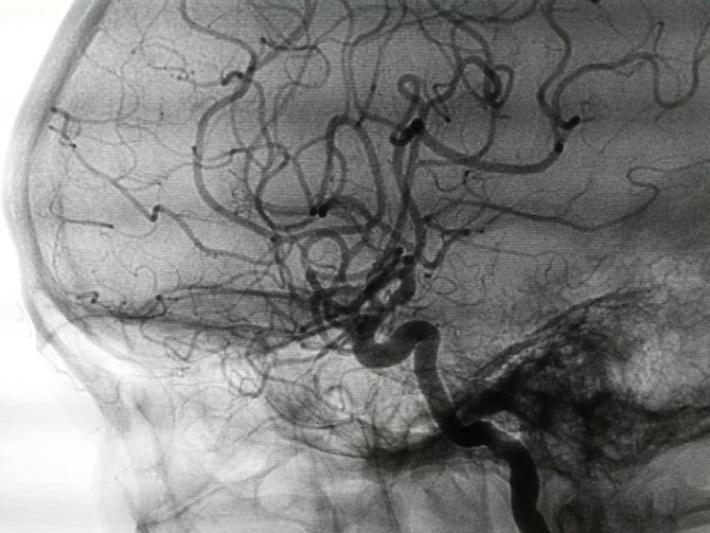

发病后6天(入院当天)DSA示:右侧前交通动脉瘤,右侧脉络膜前动脉瘤,仔细阅片,认为责任动脉瘤为前交通动脉瘤可能性大。原因如下:前交通动脉瘤约2x3mm大小,形状较狭长,瘤顶指向右侧前下方(也可解释蛛血部位)。而脉络膜前动脉瘤约1×1mm大小,形状较扁平,破裂可能性相对小些。